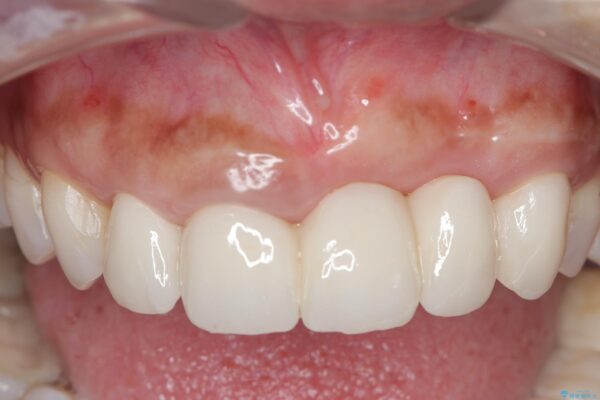

治療後

歯槽堤保存術を併用したブリッジ治療 治療後画像 歯槽堤保存術を併用したブリッジ治療 治療後画像 歯槽堤保存術を併用したブリッジ治療 治療後画像 歯槽堤保存術を併用したブリッジ治療 治療後画像 歯槽堤保存術を併用したブリッジ治療 治療後画像 歯槽堤保存術を併用したブリッジ治療 治療後画像 歯槽堤保存術を併用したブリッジ治療 治療後画像